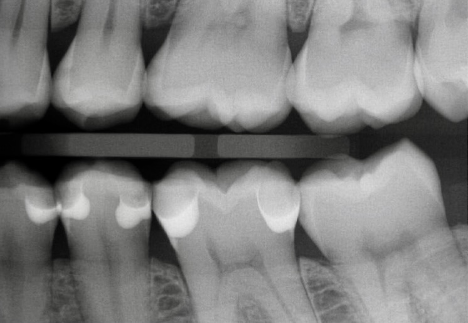

The tape is passed through one contact point of the tooth being worked on (Fig. 1), then looped around the palatal and passed through the other contact point, leaving two free ends on the facial (Fig. 2).